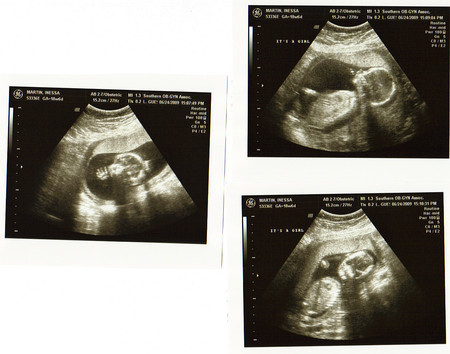

УЗИ...21 неделя 5 дней...)

БПР: 54мм

ЛРЗ: 72мм

ОГ: 199мм

ОЖ: 175мм

Длина бедренной кости: 39мм

Длина костей голени: 32мм

Длина плеч: 35мм

Длина костей предплечья: 31мм

Весим мы примерно 400 гр.